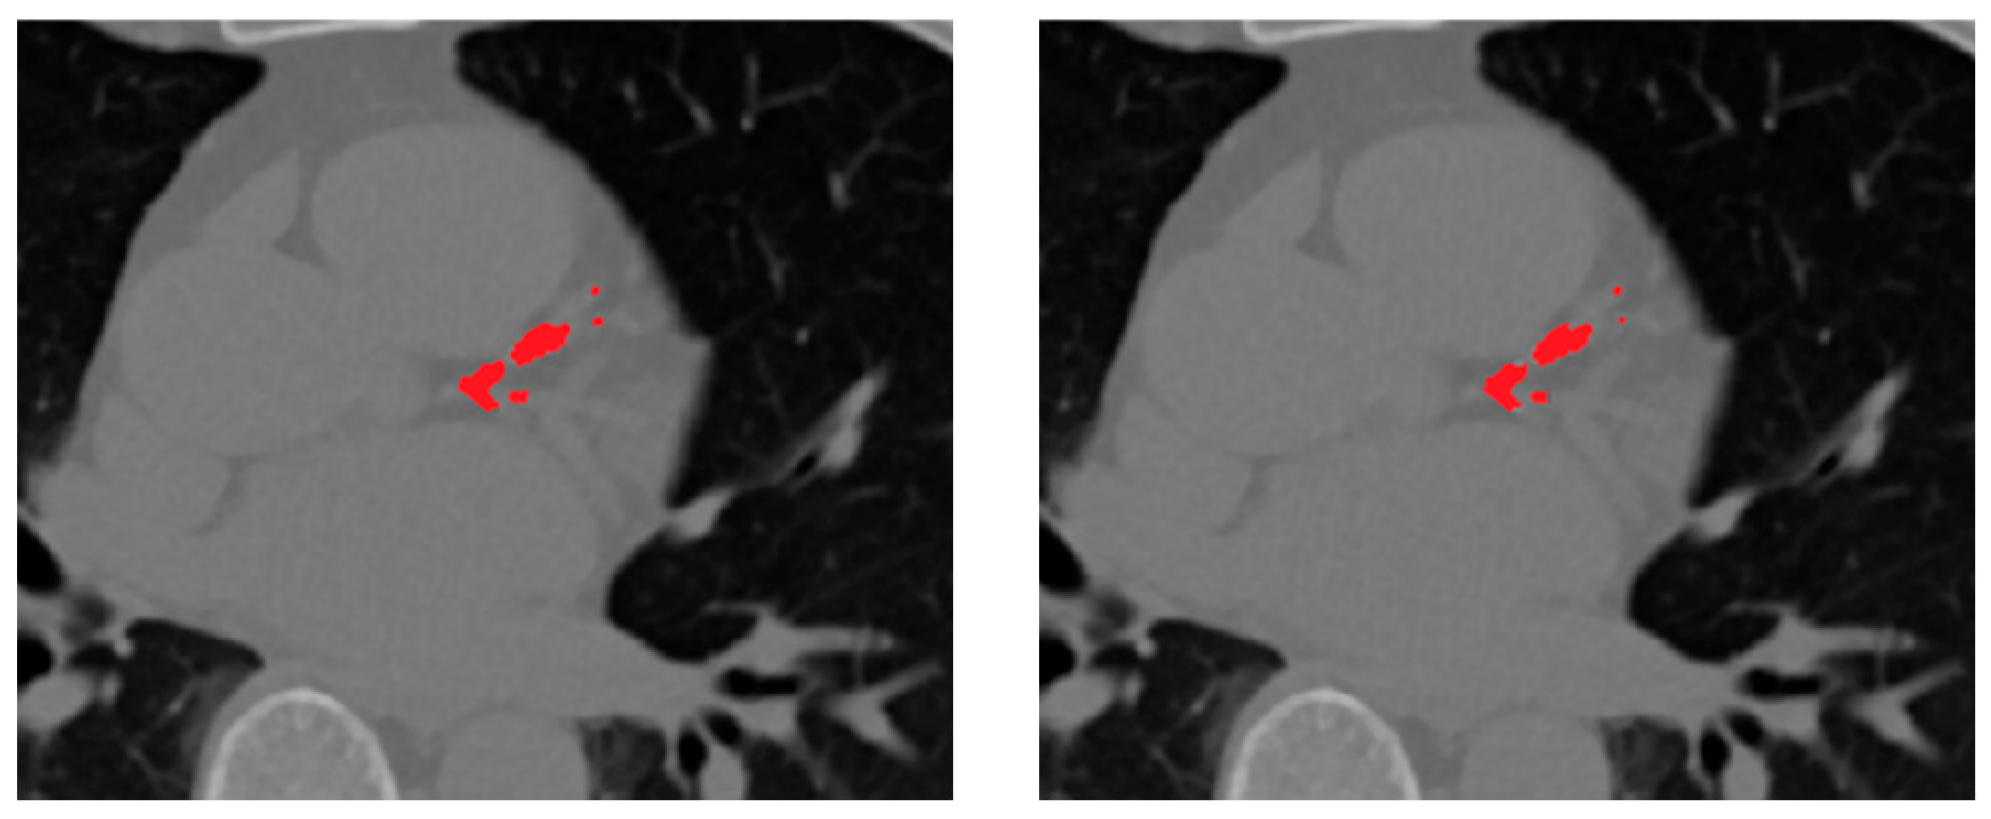

To evaluate the effectiveness of the proposed rank-based selective ensembling, we compared it against the conventional soft-voting approach, where probability maps from all ensemble members are averaged voxel-wise without spatial weighting. While simple, soft-voting treats all model predictions equally, regardless of their local anatomical plausibility or consistency, often leading to over-segmentation and blurred lesion boundaries.

As shown in Table 3, the proposed selective fusion achieves higher Dice and sensitivity while maintaining high specificity. This improvement stems from the ability of the rank-based strategy to evaluate predictions based on morphological consistency, spatial continuity, and vessel conformity. By ranking each candidate prediction relative to the vessel priors obtained in the preceding stage, the method selectively emphasizes anatomically reliable regions while suppressing fragmented or false detections outside the coronary tree.

The selective ensemble improves Dice by approximately +0.55% and sensitivity by +0.6% compared to soft-voting, demonstrating that spatially guided, vessel-aware weighting is more effective than uniform averaging. This enhancement is most evident in small or low-density calcifications, where anatomical context plays a critical role in distinguishing true lesions from background noise.

Visually, the selective ensemble produces sharper and smoother lesion boundaries and exhibits fewer false positives, especially around dense extracardiac regions such as the aorta and cardiac valves.

Figure 7 presents representative qualitative comparisons, illustrating that the selective fusion generates cleaner, anatomically coherent segmentation masks, effectively preserving true calcifications while suppressing spurious predictions. The proposed selective fusion produces more anatomically consistent calcification masks with reduced false positives and improved boundary continuity.

Figure 7. Comparison of fusion strategies for ensemble CAC segmentation. From left to right: rank-based selective ensemble output, soft-voting ensemble.